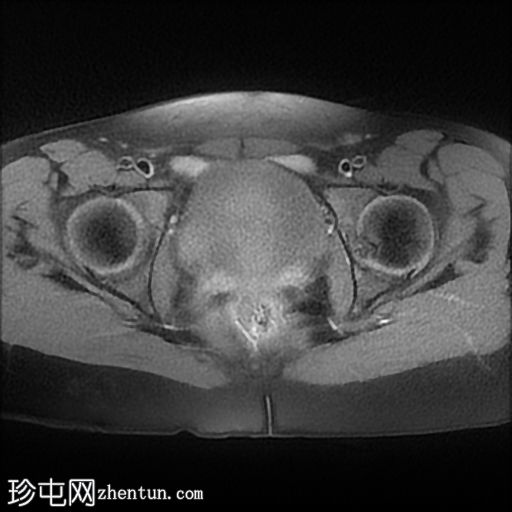

轴向

T2

子宫体相对较小,发育良好。宫颈发育不全。

阴道整体不显影,远端可见一层细小的纤维组织,在轴向和矢状面T2加权序列上最为明显。

随后,子宫内膜和宫颈腔扩张,出现混合液体/血液降解信号(积血)。它诱发中至高T1信号,伴有依赖性低信号碎片,无病理性强化。

周围轻度盆腔积液,盆腔及附件脂肪平面模糊,信号相似,增强后强化明显。这些发现提示可能有渗漏液/血液积聚,并伴有腹膜反应。

右侧附件卵巢功能性囊肿。